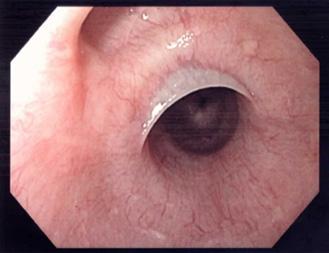

Es una infección del endocardio de las válvulas (superficie anterior).

Válvula nativa:

Las válvulas derivan embriologicamente de las almohadillas endocárdicas y el corazón del mesodermo visceral. (ENARM 2023)

Endocarditis aguda causa más frecuente estafilococo aureus (estafilococo dorado) suele afectar a las válvulas sanas por lo general, fatal en 6 semanas si no se trata

Endocarditis subaguda causa más frecuente estreptococos del grupo viridans válvulas nativas dañadas previamente causa común de después de procedimientos dentales

El flujo turbulento daña el endotelio de las válvulas activando la hemostasia y se forman vegetaciones asépticas formadas por plaquetas y fibrina (trombo estéril). Luego, estas se contaminan debido a una bacteriemia por un foco séptico, formándose una verruga bacteriana (vegetación séptica), la cual puede destruir la válvula (rotura de cuerdas tendinosas, músculo papilar) y formar abscesos, produciendo la clínica cardiaca; los émbolos sépticos que pasan a la circulación sistémica dan lugar a la clínica extracardiaca (en casos de ADVP, predominan los émbolos pulmonares).